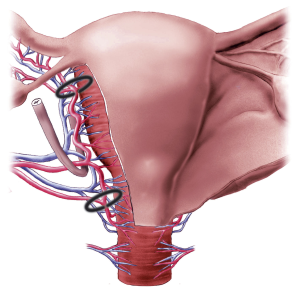

Chirurgická devaskularizace dělohy

55f28d9715bbdff6.PK_2a_1

f559648e926da6e6.PK_3a_1